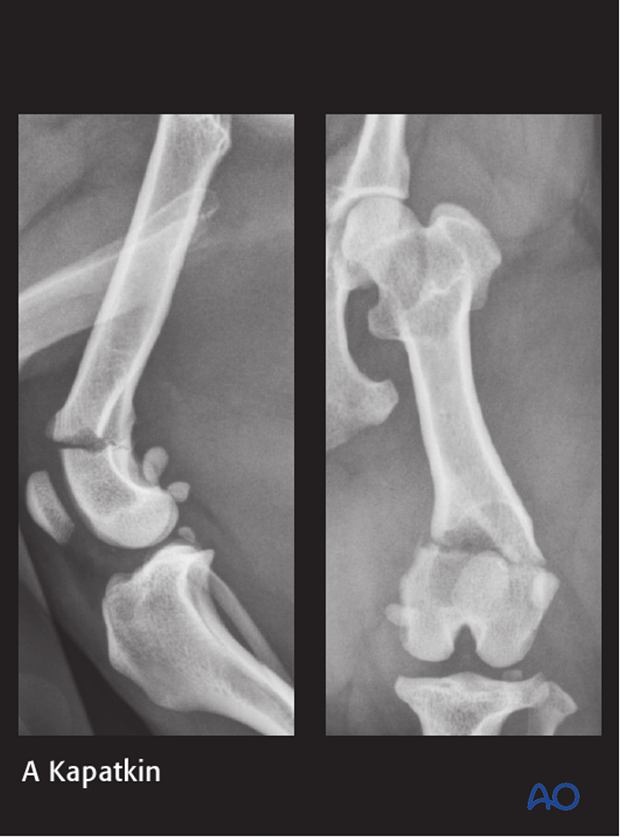

Bone plates may be placed on the lateral or medial surface of the femur. The normal curve of the distal femur makes it difficult to achieve optimal screw purchase with standard straight plates. Contouring these plates is challenging.

Numerous plate types can be used. Specially designed plates for the distal femur are available.

Ideally the plate should be long enough to place at least three screws on either side of the fracture plane. In this location, the use of only two screws in the distal fragment is acceptable.

The plate is contoured to the lateral aspect of the distal femur. The plate position and contouring to the bone is checked thoroughly and adjusted, if required.